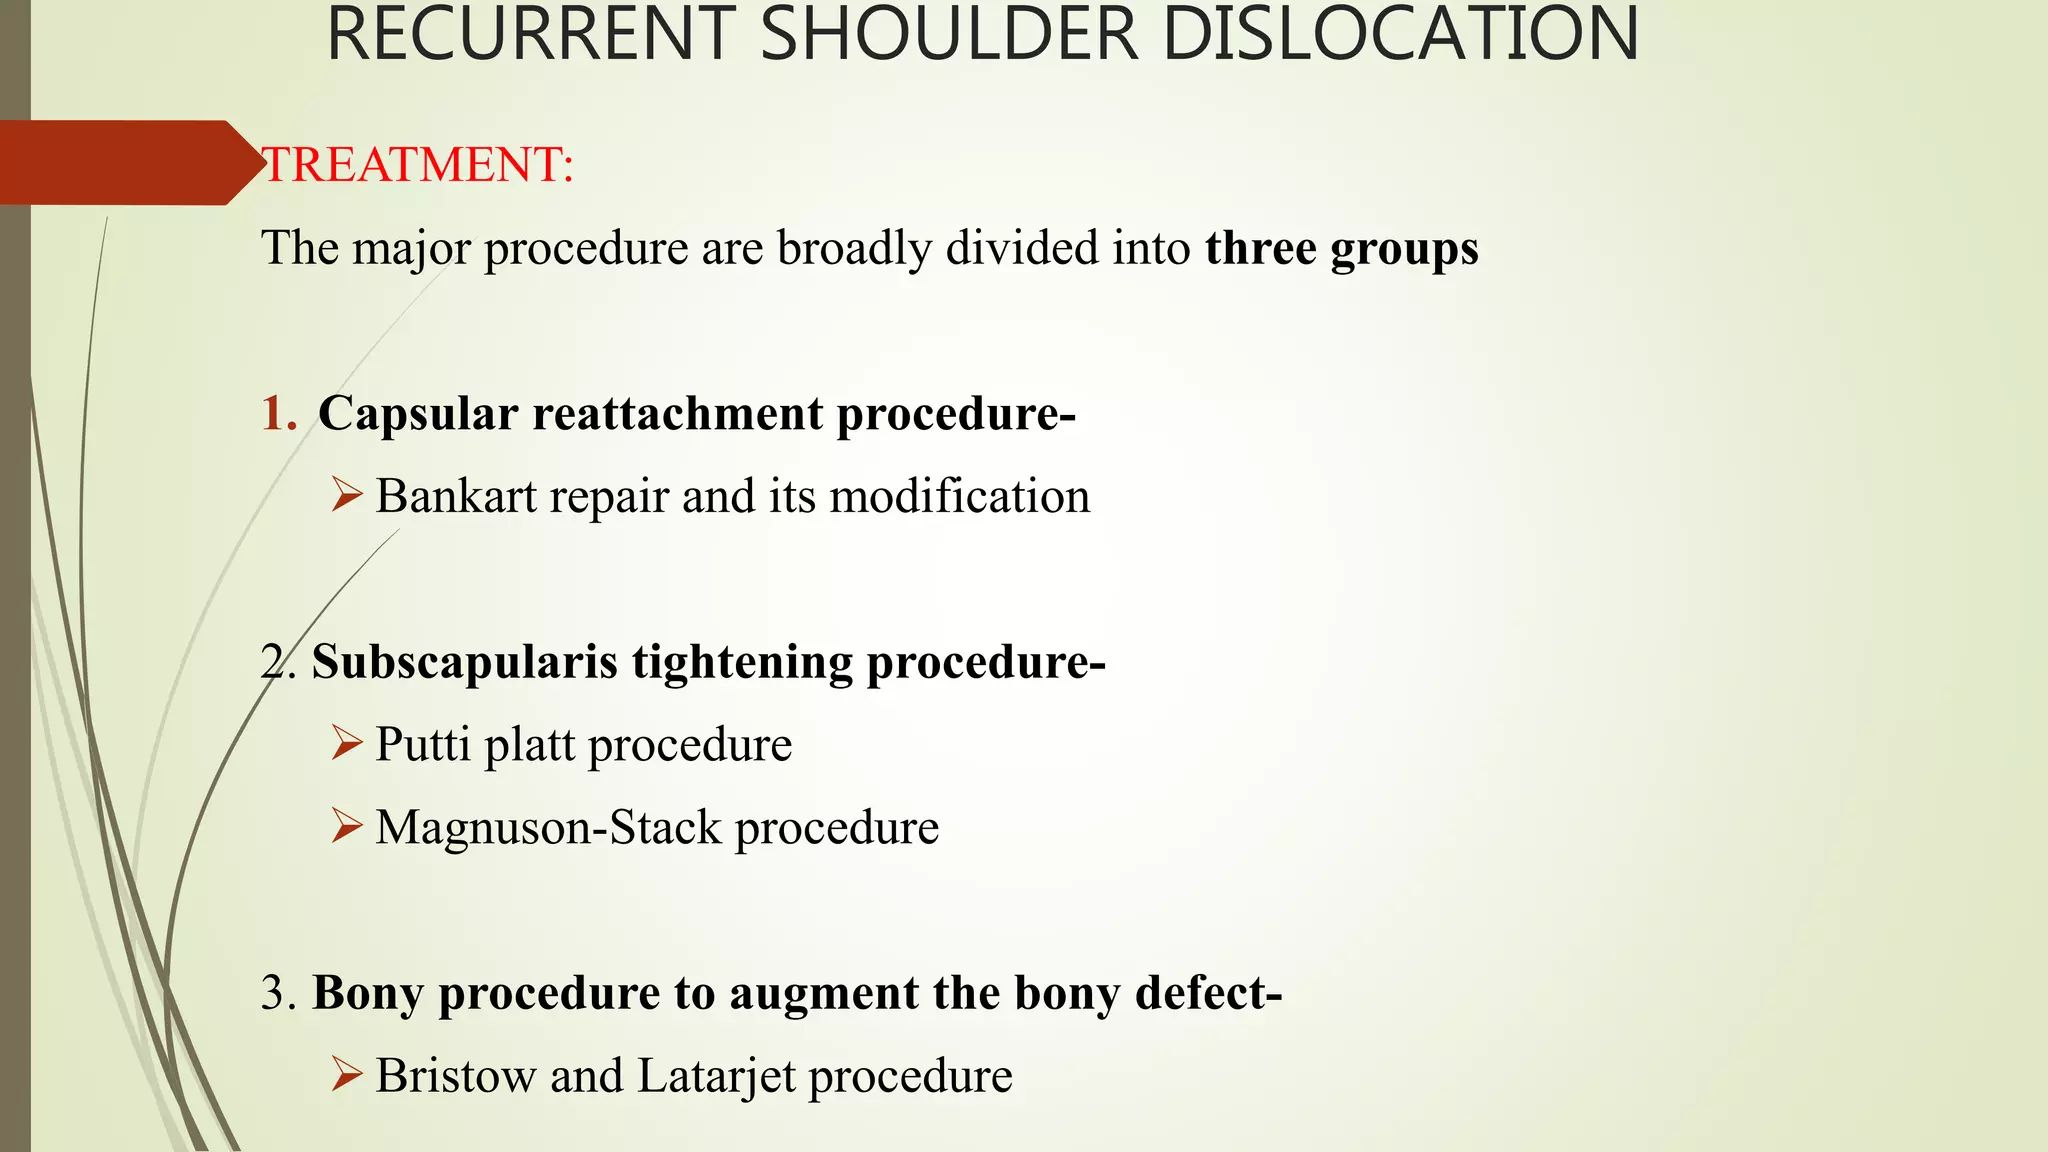

- Treatment involves closed reduction for most acute dislocations. Recurrent or complicated dislocations may require surgery and immobilization followed by physical therapy.